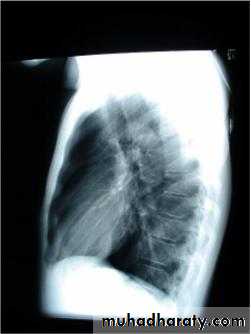

• Radiological Findings

• 1-Smooth homogenous opacity (Intact H.C).• 2-Partial rupture (per vesicular pneumocyst).

• 3-Complete rupture (Water –lilly sign) .

• 4-Formation of lung abscess(Air –fluid level) .

• 5-Completely coughed out cyst(empty cavity )

• 6-Rupture into the pleura (hydropneumothorax)